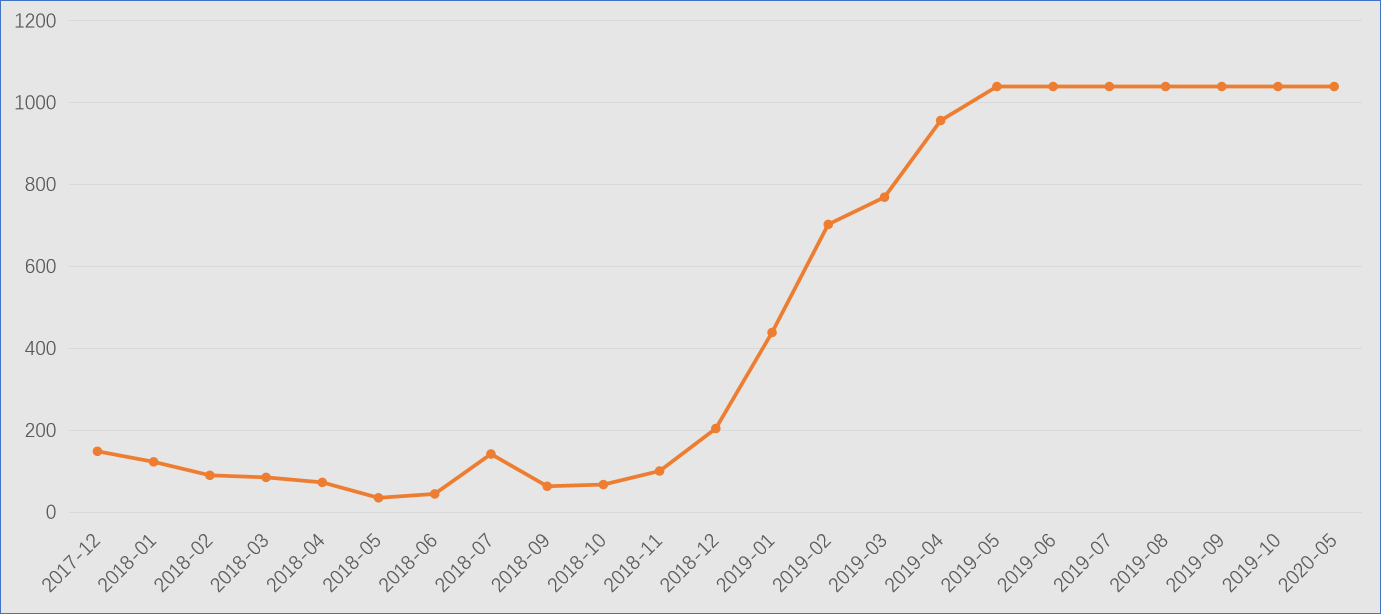

CEA:2017-12至2020-05

肿瘤标志物:CEA>1022ng/ml、其余正常。